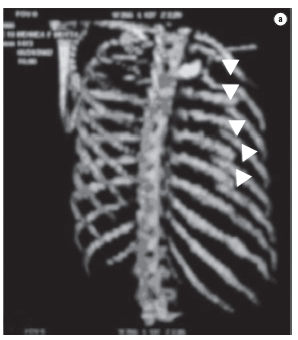

Paciente do sexo feminino, 32 anos, vítima de acidente automobilístico, que ocasionou hemopneumotórax esquerdo, contusão pulmonar esquerda e fraturas duplas do terceiro ao oitavo arcos costais esquerdos, evidenciados na radiografia e tomografias computadorizadas (TC) do tórax (Figuras 1 e 2). As tomografias de crânio, coluna cervical, abdômen e pelve apresentaram-se normais, assim como eletrocardiograma, ecocardiograma, enzimas musculares e marcadores de necrose miocárdica. Foi realizada drenagem torácica fechada em selo d'água e solicitada a instalação de cateter epidural para analgesia contínua com bomba de infusão. A paciente apresentava deformidade torácica importante e dor, apesar de doses elevadas de analgésicos. Antecipou-se que o quadro, se não tratado cirurgicamente, evoluiria para deformidade complexa da parede, com possível acometimento da respiração. Não necessitou de ventilação mecânica. Em vista desse quadro clínico, foi decidido o tratamento cirúrgico para estabilização das fraturas. O procedimento foi realizado por toracotomia póstero-lateral esquerda. Foram encontradas fraturas duplas do terceiro ao oitavo arcos costais esquerdos com ruptura completa de vários pedículos intercostais, herniação e impactação do segmento fraturado (6 arcos) para o interior da cavidade pleural, com compressão importante do parênquima pulmonar (toracoplastia traumática). Foi realizada redução das fraturas e fixação das costelas com fios de aço número 5, perfurando as extremidades das costelas com broca número 2, passando-se o fio de um segmento de costela para outro e amarrando-se o fio de aço. Foi colocado um dreno de tórax, que foi retirado no terceiro dia. A paciente evoluiu com excelente controle da dor e melhora na dinâmica ventilatória. A radiografia e a tomografia no pós-operatório confirmam o bom resultado do tratamento cirúrgico. (Figura 3).